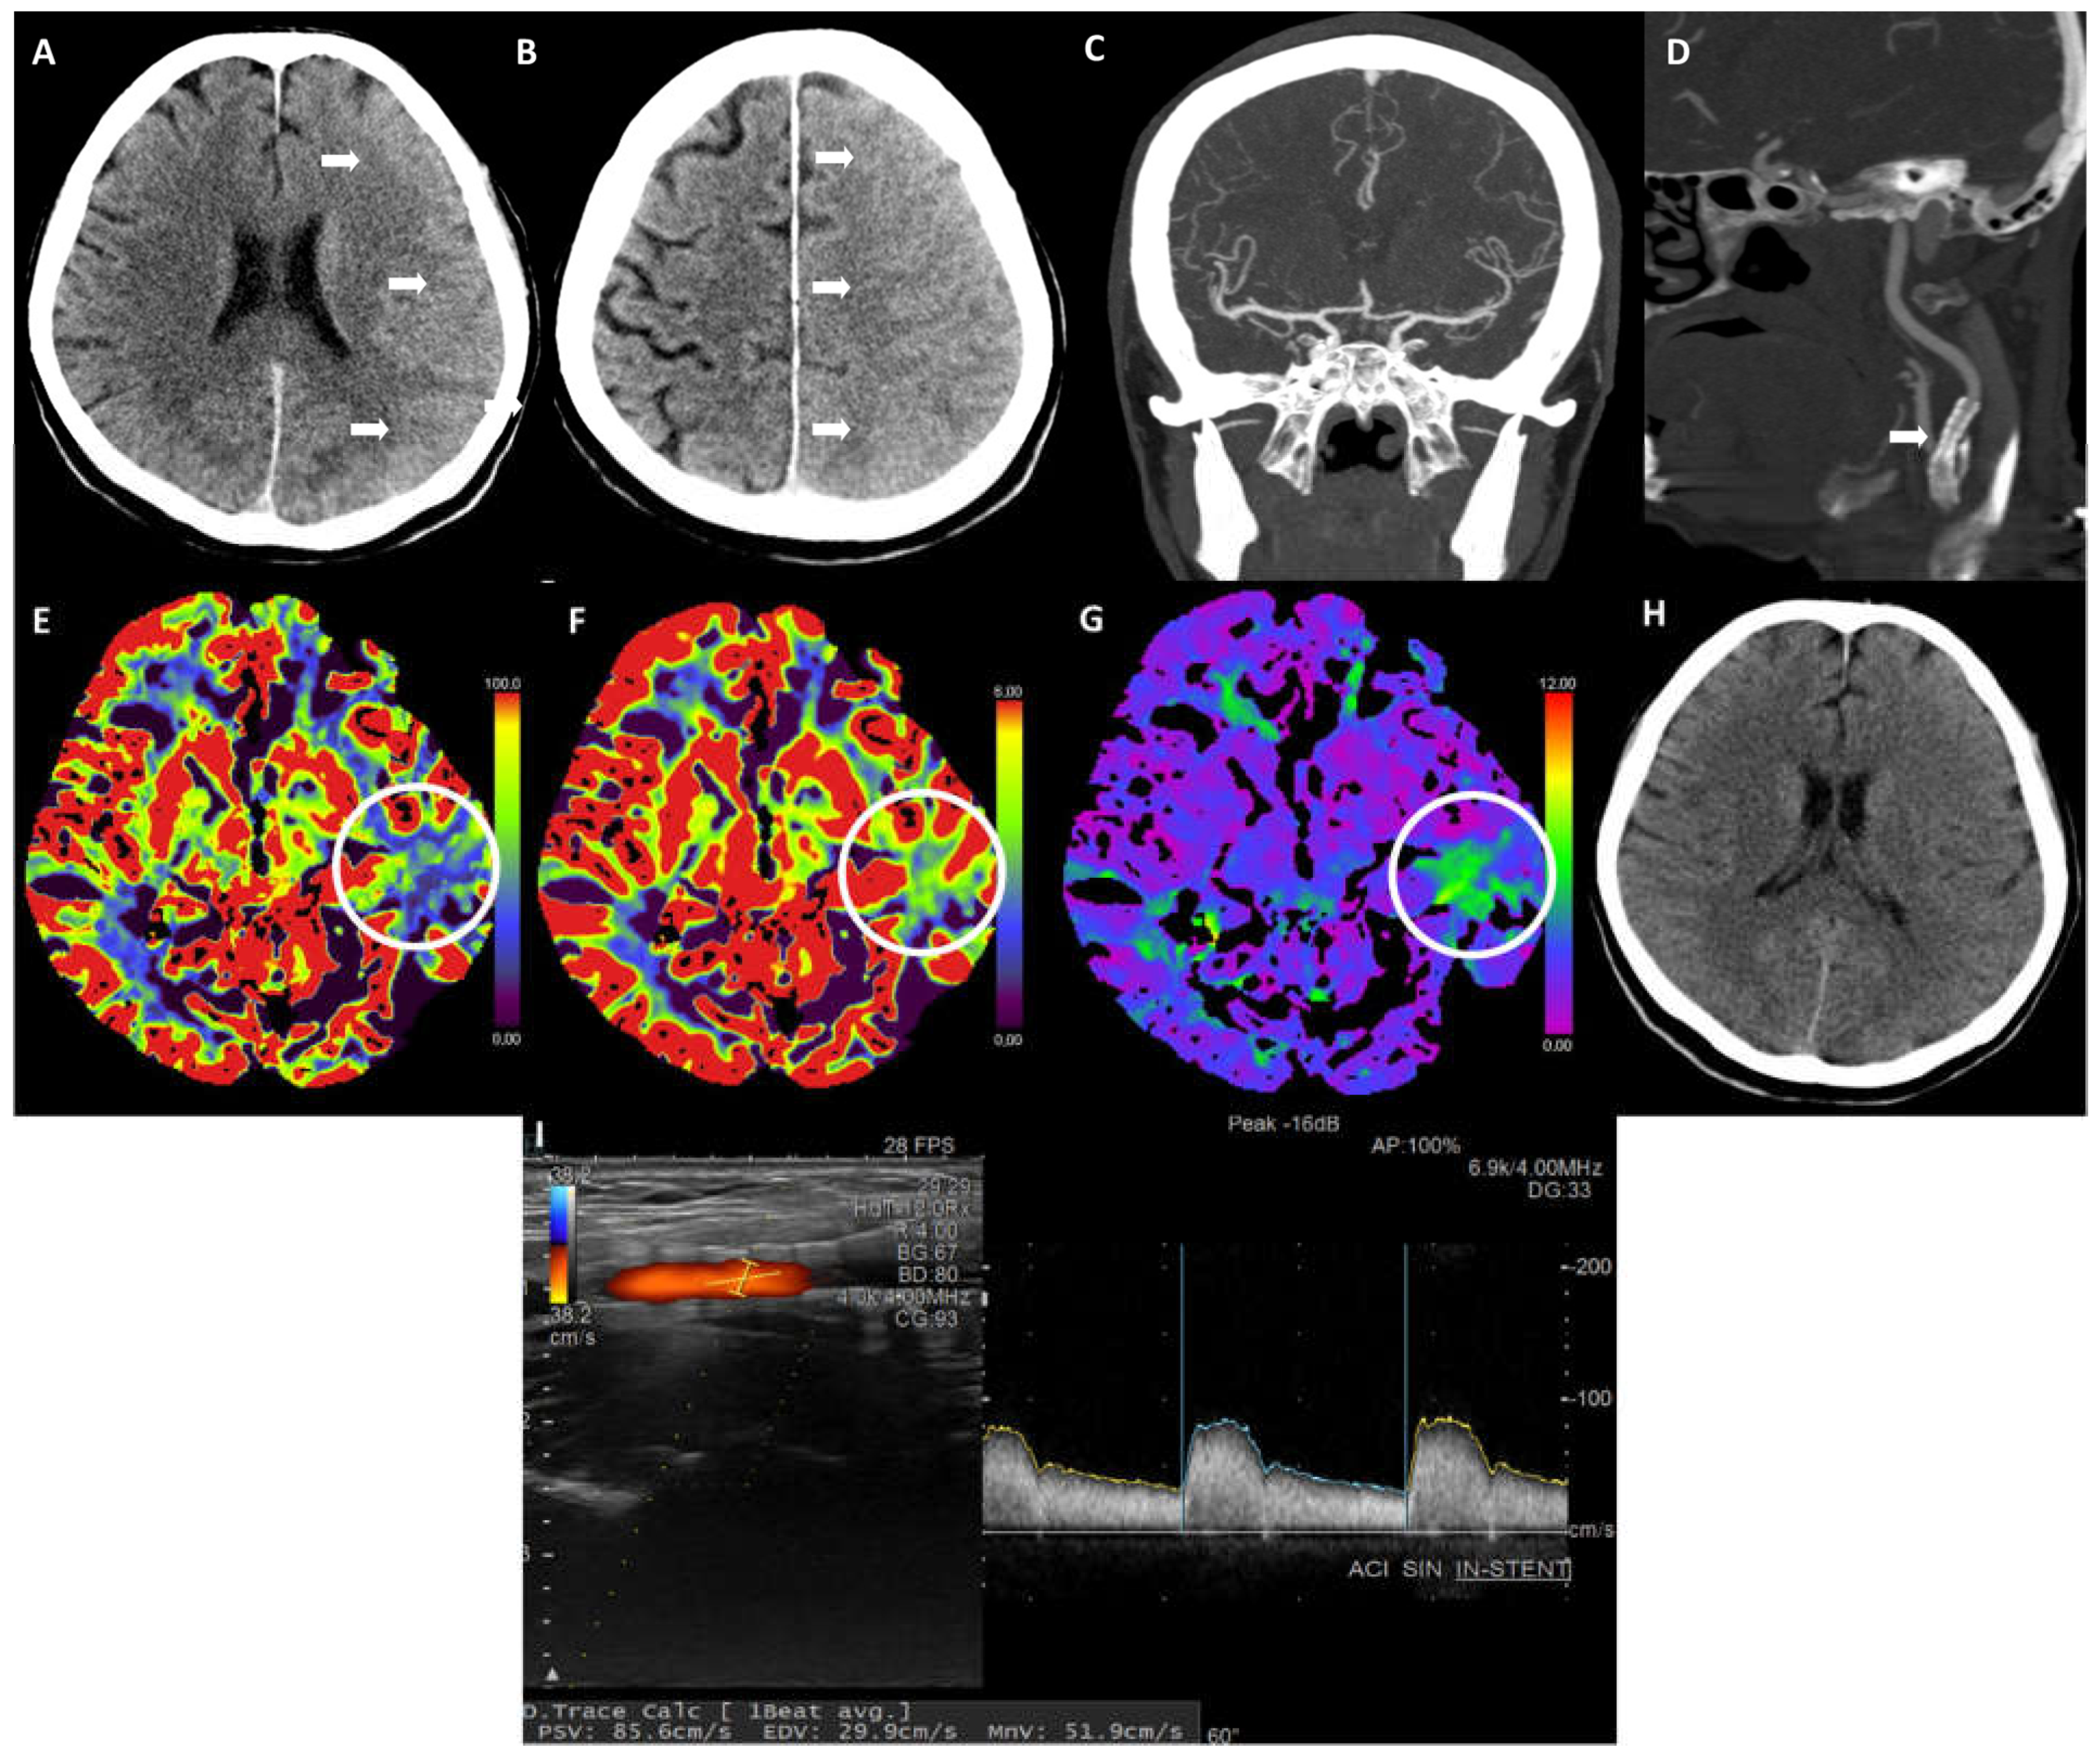

2. Case Report